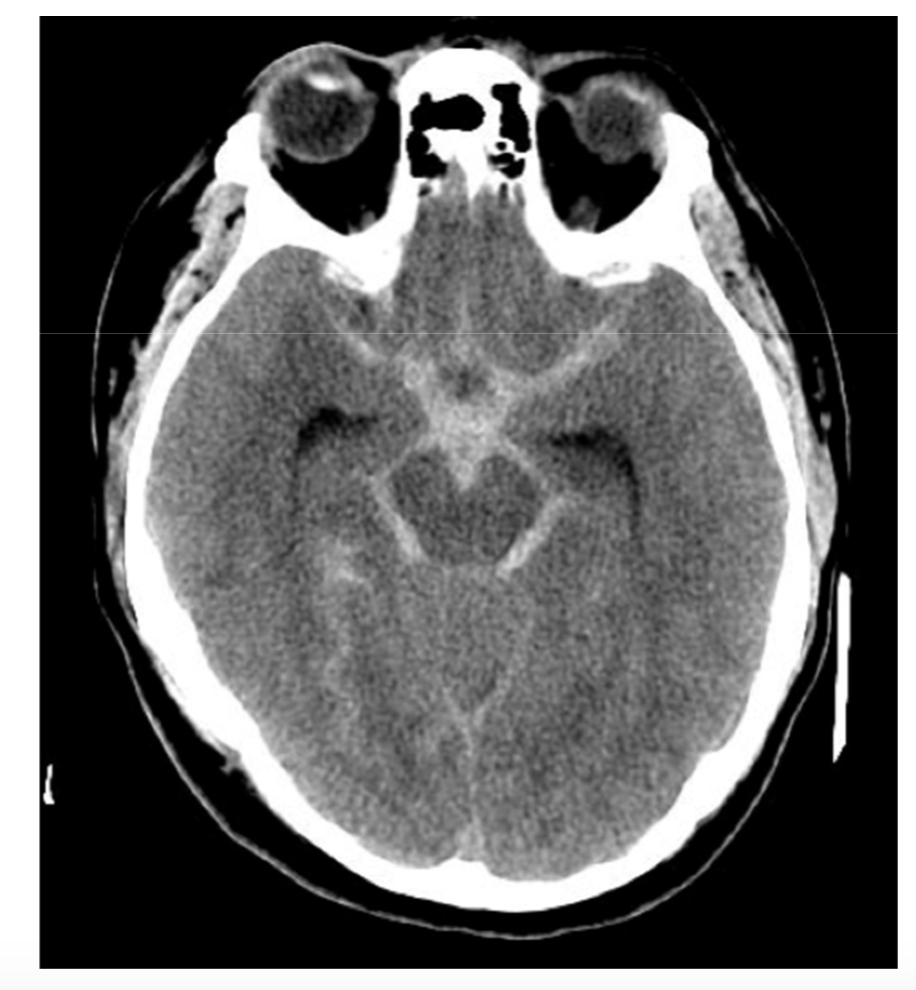

If you suspect a SAH in a patient, what are your next steps?

A

• CT

• highest sensitivity w/in 6 hr

• Lumbar puncture

• xanthrochromia (not present until 2 hrs - can last 2 weeks)